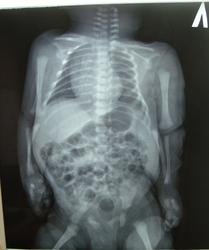

Ребенок  возраст 2 дня

роды 2 кесарево сечение срок 38 недель

после осмотра невролога и УЗИ ГМ DS Церебральная ишемия 1 ст Парез Дюшена- Эрба слева

Не спец по детям, но, кажется, есть вывих локтевой кости левого локтевого сустава и правого тазобедренного.

целесообразно ли говорить об эпифизеолизе Коллеги???

Мне кажется, что здесь вывихи, а не эпифизеолиз.

Не нравится соотношение костей в левом локтевом суставе, как будто вывих. Надо бы в стандартных проекциях переснять.

Учитывая ассиметрию укладки достоверно сложно сказать. Снимите левый локоть в двух стандартных проекциях. Остальное тело только заэкранируйте.

сегодня проводили УЗИ локтевых суставов

заключение эпифизеолиз слева подтвержден

проведена репозиция под контролем УЗИ - ну и гипс

по поводу тазобедренного сустава справа есть мнения?

Тазобедренные суставы надо бы отдельно переснять. Но лучше не рентген, а (для начала) УЗИ.

Эпифизиолиз чего? если не секрет.

УЗИ-ты молодцы однако. Потому что по этому снимку эпифизиолиза никак не увижу. Лучевой нагрузкой только рентгенологи беспокоятся. У нас такая же ситуация. Рентгенография ОГП, согласно стандартам, показана всем новорожденным с дыхательными расстройствами (ну это я в общем, не принимая во внимание данный случай). А выход патологии 10% максимум.

цель по всей видимости исключить травму, так как имеет место родовая...

а по диагнозу - сросшийся чрезмышелковый перелом плечевой кости

Сросшийся? У ребенка в 2 дня жизни? surprise Ничего уже не понять с вашим случаем...

ребенок находился в перинатальном центре после родов как оказалось теперь с переломом 10 дней

3 января переведен в специализированный стационар проведена репозиция

тк травматолог и рентгенолог патологию не заподозрили

невролог выставила DS парез дюшена эрба слева

снимок который представлен от 26 числа ребенок родился 24

репозиция 3 января

те с 24 по 3 января - 10 дней можно сказать без диагноза